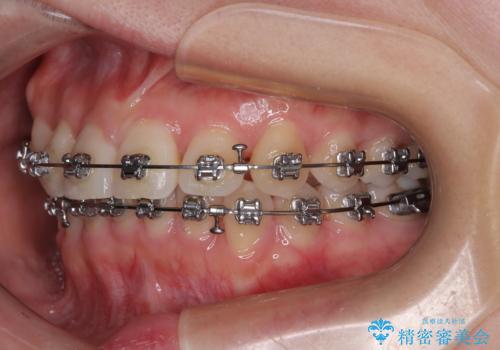

捻転の強い前歯 ワイヤー装置での非抜歯矯正

- 矯正装置

- メタルブラケット

マウスピースでもワイヤーでも対応可能でしたら、捻転が非常に強いことから、患者様と相談の上ワイヤー装置にて矯正治療を行うこととしました。

捻転を解消する際に、歯列全体が前方に突出して出っ歯の仕上がりとなることが懸念されたため、補助装置を用いて上顎歯列全体を後方に移動する力をかけることとしました。

適合や携帯の悪いプラスチックのクラウンが装着されていたため、矯正治療後にオールセラミッククラウンによる補綴治療を行うこととしました。